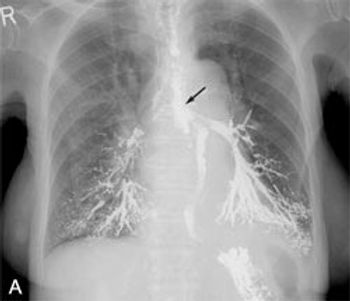

Abstract: A number of factors can complicate the diagnosis of asthma in elderly patients. For example, the elderly are more likely to have diseases such as chronic obstructive pulmonary disease (COPD) and congestive heart failure (CHF) that--like asthma--can cause cough, dyspnea, and wheezing. Spirometry can help distinguish asthma from COPD, and chest radiography and measurement of brain natriuretic peptide levels can help identify CHF. Important considerations in the management of asthma include drug side effects, drug interactions, and difficulty in using metered-dose inhalers. When discussing the goals of therapy with the patient, remember that quality-of-life issues, such as the ability to live independently and to participate in leisure activities, can be stronger motivators than objective measures of pulmonary function. (J Respir Dis. 2006;27(6):238-247)